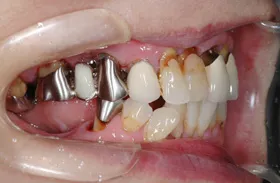

他院で「歯槽膿漏は治らない」と言われ、当院にご来院されました。歯が乱ぐいのため、歯並びもよくしたい、下は歯を既に失っているので噛めるようにもなりたい、またコーラスをされていて人前で口をあけることが多いので、できるだけ見た目を意識した治療をしてほしいとのご要望でした。

■治療前